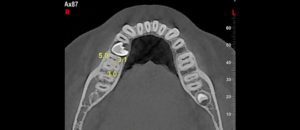

228 – Impacto de la CBCT en la toma de decisión del tratamiento relacionado a extracción de terceros molares impactados.

El objetivo del presente estudio fue evaluar los factores (referidos a la CBCT) que influyen en la toma de decisión en tratamientos para extracción de